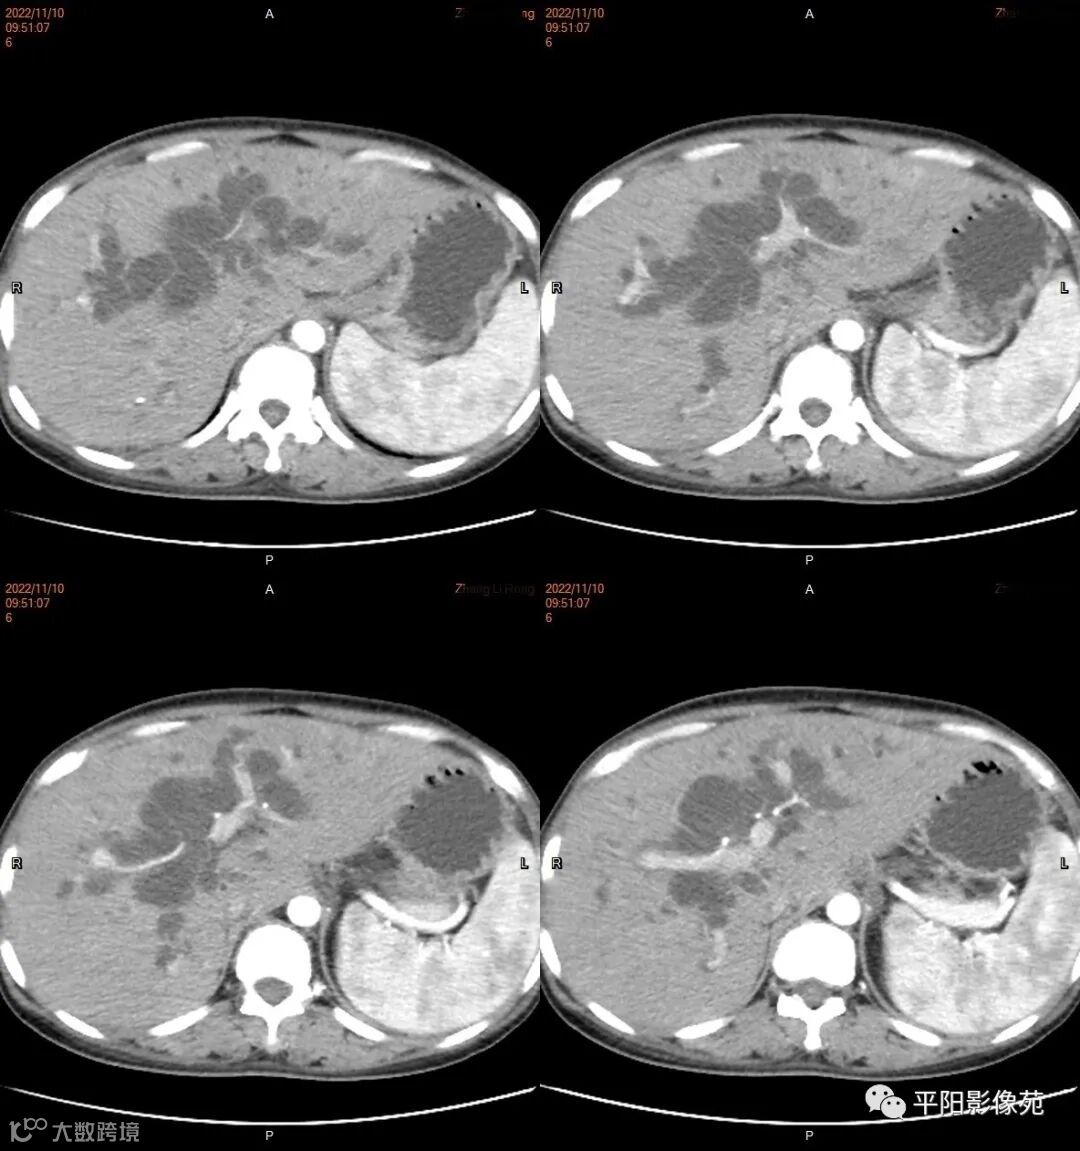

影像学检查

CT

影像表现: